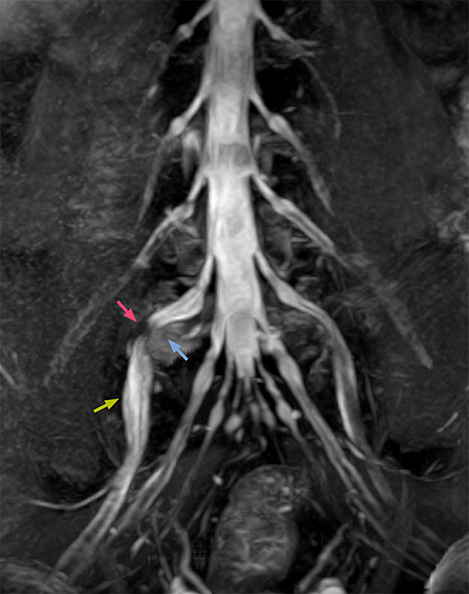

“NerveVIEW can clearly show nerve courses and presence of nerve compression. However, when multiple abnormalities are seen, it can still be hard to determine which nerve is causing the symptoms,” says Dr. Yabuki. “In our experience so far, we see abnormal findings on NerveVIEW in about 70% of elderly patients. As the pain is usually caused by only one nerve, we thus need to find the exact corresponding nerve.” “With a nerve root block, the patient's pain is improved by infiltration of local anesthesia directly around the nerve root considered to be responsible. Knowing such nerve root block findings prior to image interpretation, helps to easily recognize abnormal findings on NerveVIEW as well. In other words, without a priori knowledge, based on symptoms and/or nerve root block findings, we must be aware of the possibility of overdiagnosis.”

The addition of the nerve-selective NerveVIEW sequence to its spine MRI protocol has given NFMC competitive advantages, according to Tanji. “Since we started including NerveVIEW routinely, the demand for lumbar spine MRI examinations has increased, especially for pre-surgical planning purposes and for patients with chronic lower extremity symptoms,” he says. “Moreover, because no other hospitals in our region are doing nerve plexus imaging yet, we often receive referrals for MR neurography studies from other hospitals even if they have an MRI scanner. Some requests come from as far as 100 km away. NerveVIEW definitely provides us a competitive advantage.” “Based on our experience, we can certainly recommend NerveVIEW to other centers,” Dr. Yabuki adds. “The sequence opens up many possibilities to facilitate the diagnosis of lower extremity pain and to inform our decision-making regarding therapy and surgery.”